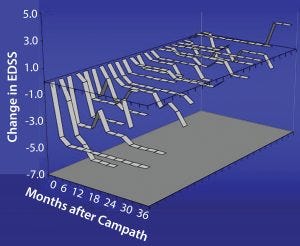

Studies have shown for some time that Campath-1H could be used for treating multiple sclerosis (Figure 6). The treatment has been over a course of only five days, followed by another five-day treatment one year later. During treatment, which depletes lymphocytes and powerfully immunosuppresses patients, the instances of adverse clinical events were greatly reduced. In addition, the patients’ levels of disability seemed to improve (Figure 7). Results from a follow-up study show that clinical improvement was maintained 10 years later.

Figure 7: Change in disability after Campath for relapsing remitting group, which showed a decrease in EDSS (less disability with time); damage to axons is not so severe, and there may be repair of the myelin sheath with consequent

improvement in function.